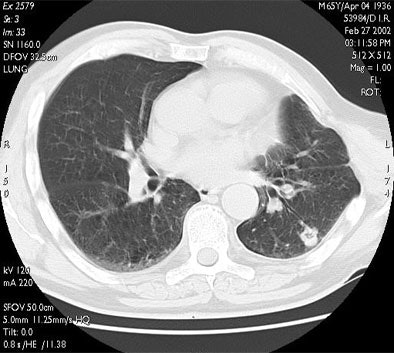

"Here you can see one of the cases with a one-year follow-up. The tumor is replaced by a volume of coagulation, which is in excess with respect to the size of the native lesion, and then at three months, six months, and one year there is progressive shrinkage of the coagulation, with some cavitation detectable on CT," he said.

![]() |

| RF ablation of stage IA non-small cell lung cancer (NSCLC). Above: Pretreatment CT scan shows solitary small NSCLC of left lower lobe. Below: At CT obtained one month after RF ablation, a ground-glass density ablation zone replacing the lesion and 1-cm of surrounding pulmonary parenchyma is detected. Images courtesy of Dr. Riccardo Lencioni. |